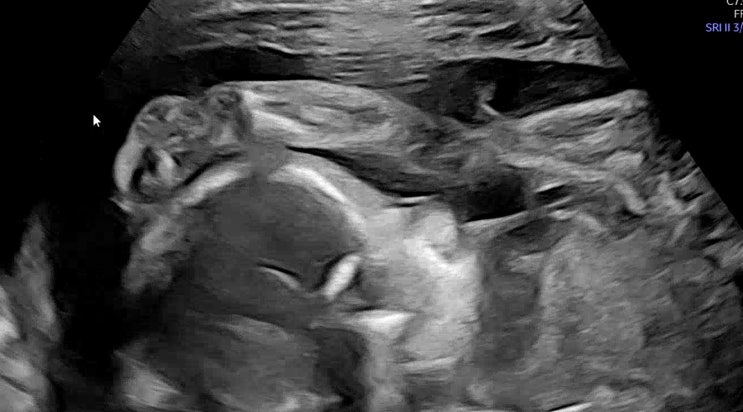

[임신일기10] 입체초음파 시기 & 정밀초음파 차이점 제일산본병원

[임신일기8] 21주 6일 정밀초음파 산본제일병원

제일 처음 초음파실에 들어갔는데, 우리 아기가 폴더 자세로 이렇게 완전 반으로 접혀 있었어요 ㅋㅋㅋ 머...